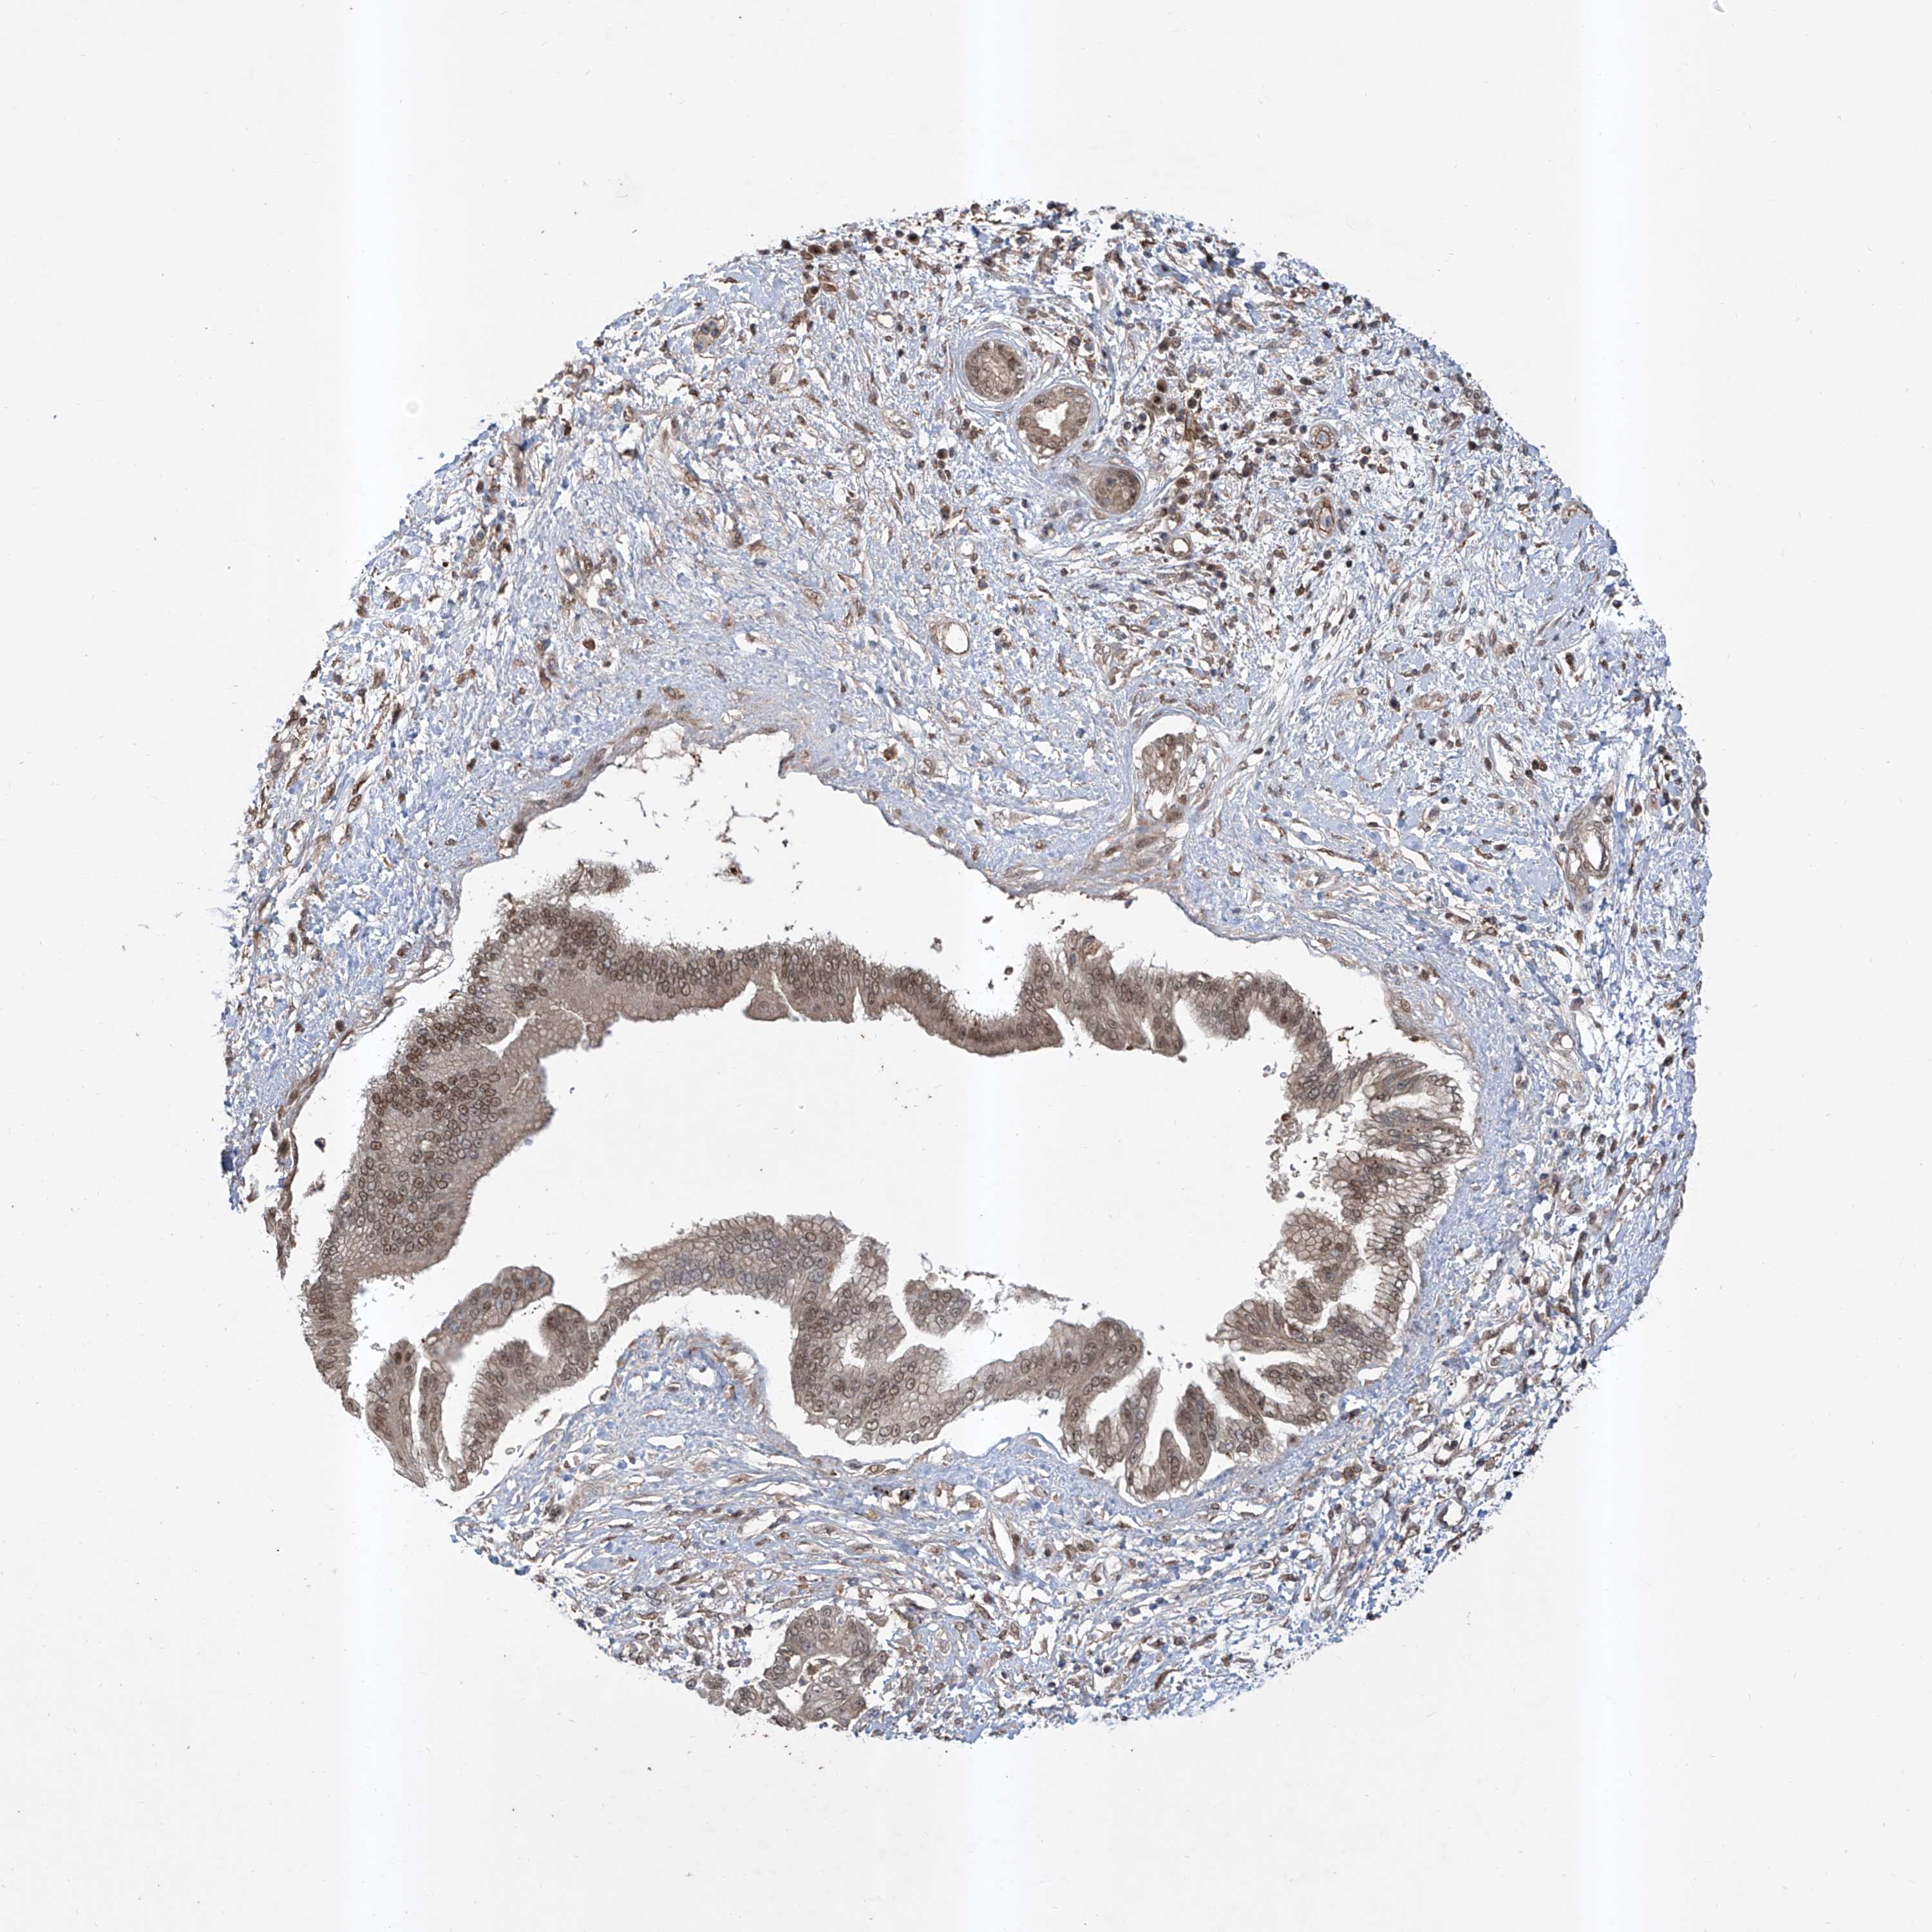

PANCREATIC CANCER - Protein expressioni

A mouse-over function shows sample information and annotation data. Click on an image to view it in a full screen mode. Samples can be filtered based on level of antibody staining by selecting one or several of the following categories: high, medium, low and not detected. The assay and annotation is described here.

Note that samples used for immunohistochemistry by the Human Protein Atlas do not correspond to samples in the TCGA dataset.

Antibody stainingi

Antibody staining in the annotated cell types in the current human tissue is reported as not detected, low, medium, or high, based on conventional immunohistochemistry profiling in selected tissues. This score is based on the combination of the staining intensity and fraction of stained cells.

Each image is clickable and will lead to virtual microscopy that enables deeper exploration of all samples and also displays staining intensity scores, fraction scores and subcellular localization as well as patient and tissue information for each sample.

Antibody HPA028911

Antibody CAB037020

Staining

High

Medium

Low

Not detected

Intensity

Strong

Moderate

Weak

Negative

Quantity

>75%

75%-25%

<25%

None

Location

Nuclear

Cytoplasmic/membranous

Cytoplasmic/membranous,nuclear

Adenocarcinoma, NOS